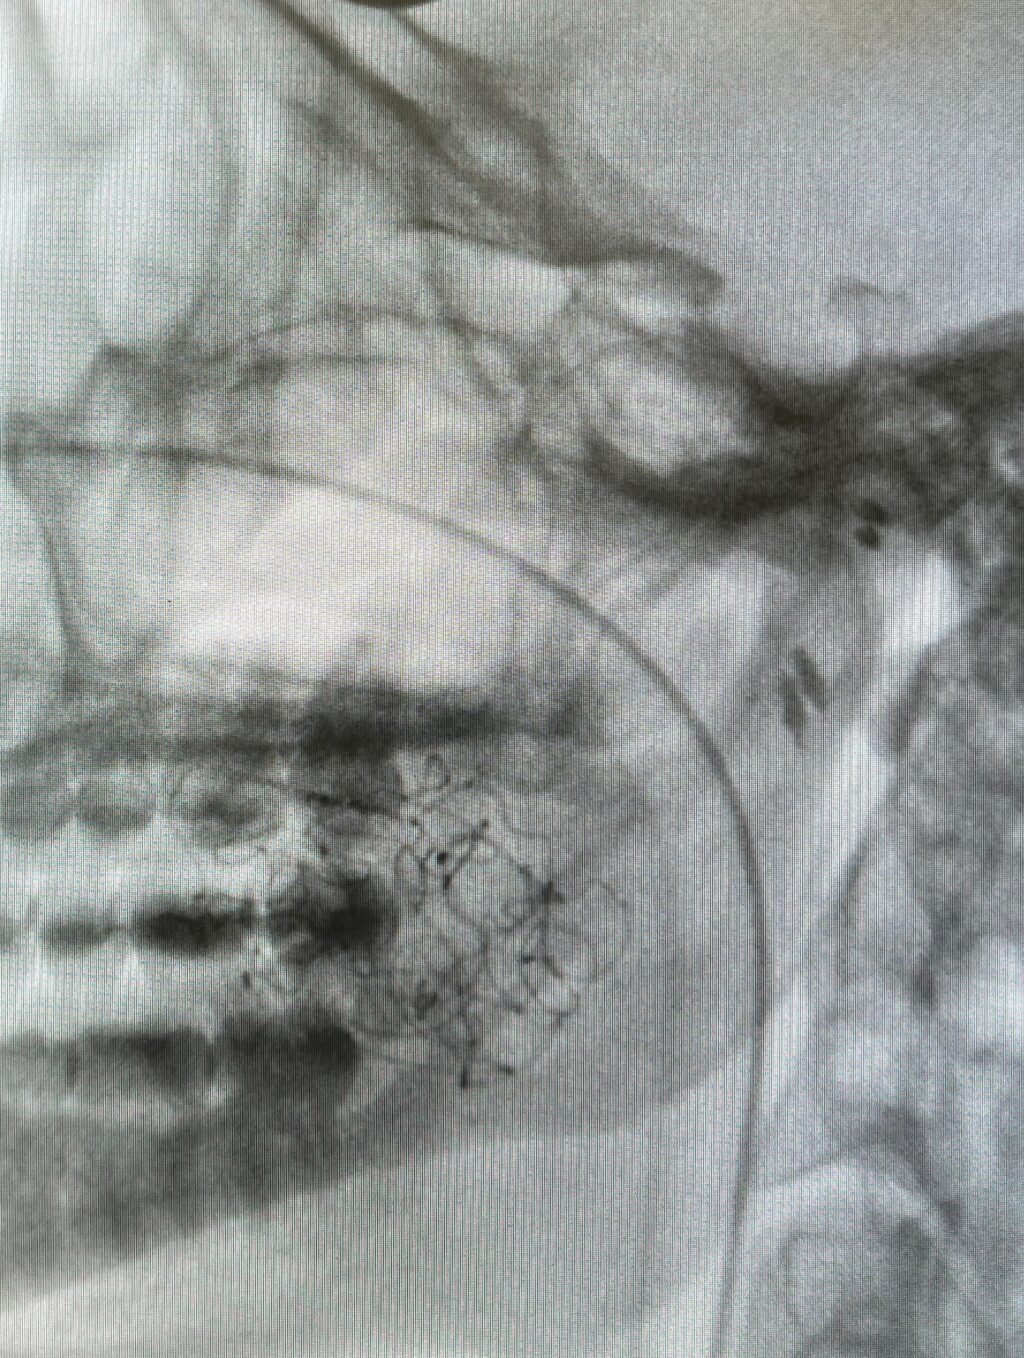

A Patologia Oral e Maxilofacial é a especialidade responsável pelo diagnóstico e tratamento de doenças que afetam a boca, mandíbula e estruturas faciais. Atua na identificação de lesões, cistos e tumores, garantindo diagnóstico preciso e tratamento adequado para preservar a saúde bucal e geral do paciente.